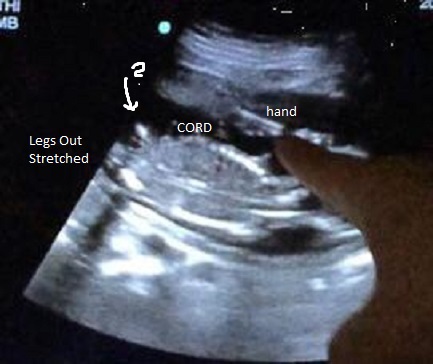

I had posted a few weeks ago that I went for a korean scan off post, it lasted 1:56 and the lady said she didnt she penis. Ok, well I had my 17 wk check up and Dr asked if I wanted to see baby. Of course!! Baby was moving like crazy and she couldn't get an actual potty shot but I have a few shots. So, I took video and these pictures are from the video.

My question, Do you see any gender clues? Skull??? Thank you for looking!!!

Baby looking up, head on right.